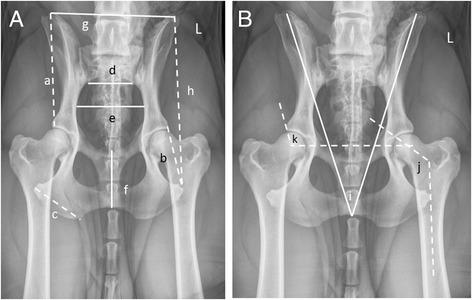

Concentrated breeding effort to produce various body structures and behaviors of dogs to suit human demand has inadvertently produced unwanted traits and diseases that accompany the morphological and behavioral phenotypes. We explored the relationship between pelvic conformation and canine hip dysplasia (HD) because purebred dogs which are predisposed, or not, to HD share common morphologic features, respectively. Thirteen unique bilateral anatomical features of the pelvis were measured on 392 dogs of 51 breeds and 95 mixed breed dogs. Principal components (PCs) were derived to describe pelvic morphology. Dogs were genotyped at ~183,000 single nucleotide polymorphisms and their hip conformation was measured by the Norberg angle and angle of inclination between the femoral neck and diaphysis.

为满足人类需求而进行的集中繁殖努力,旨在培育出具有各种身体结构和行为特征的犬类,但无意间产生了一些不良特征和疾病,这些特征和疾病伴随着犬类的形态和行为表型。我们探究了骨盆形态与犬髋关节发育不良(HD)之间的关系,因为易患或不易患HD的纯种犬分别具有共同的形态学特征。我们对51个品种的392只犬和95只混种犬的骨盆13个独特的双侧解剖特征进行了测量。通过主成分分析(PC)来描述骨盆形态。对犬进行了约183,000个单核苷酸多态性的基因分型,并通过诺伯格角和股骨颈与骨干之间的倾斜角来测量它们的髋关节形态。